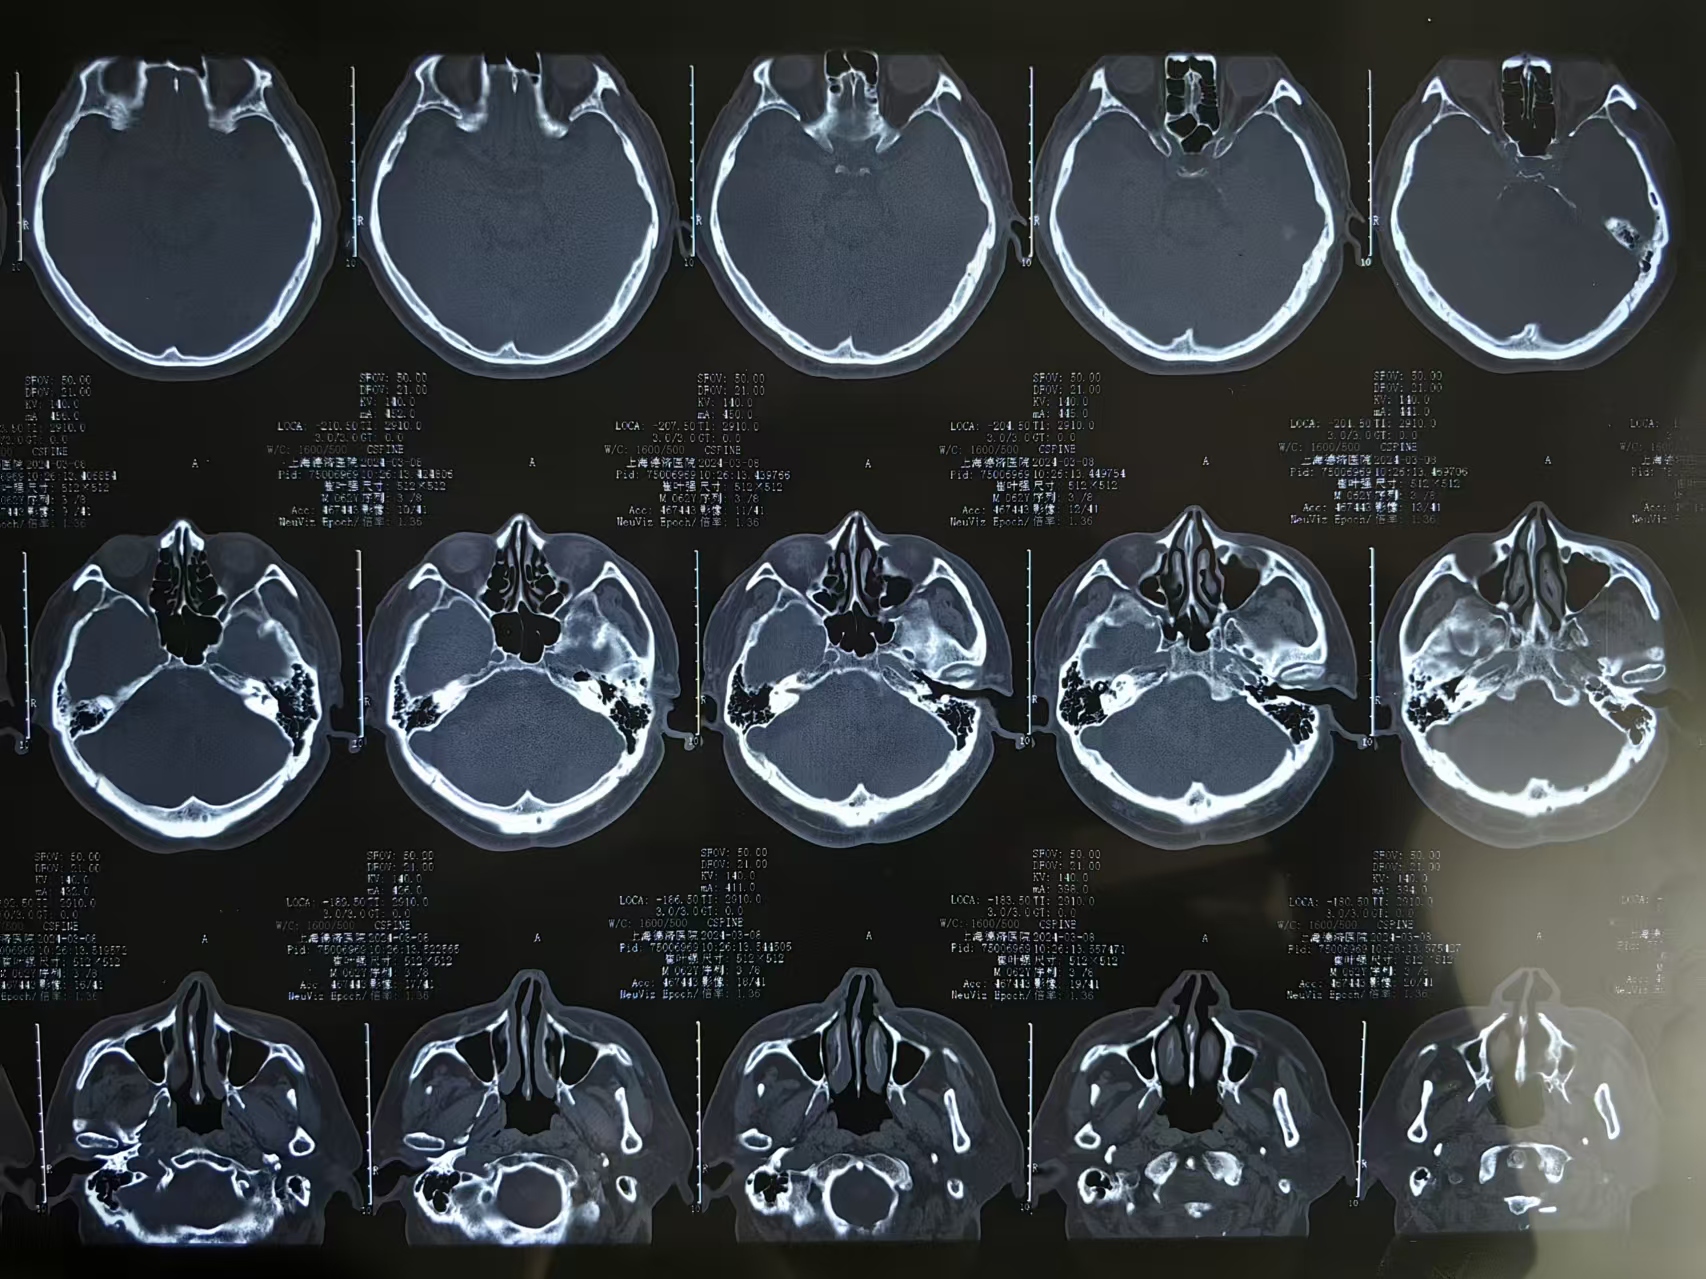

• 诊断:寰枢椎脱位,颅底凹陷

• 影像:

• 术后影像: